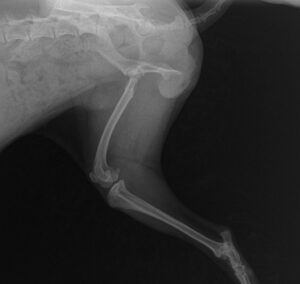

La luxation de la rotule

Elle correspond au déplacement anormal de la rotule du caniche, lors de mouvements de flexion / extension, qui n’a alors plus de contact avec le fémur. Elle peut entrainer une défaillance ou une rupture d’un ou plusieurs ligaments suivant le grade.

La luxation médiale de la rotule est une pathologie du genou se trouvant vers l’intérieur du genou. La luxation latérale est vers l’extérieur.

Nous vous conseillons toujours d’éviter de faire trop courir votre chiot caniche ou de le faire monter et descendre les escaliers, pour préserver la santé du caniche attention aussi au canapé bien trop haut quand le chiot caniche est encore très jeune.

La Dysplasie des hanches :

Elle provient d’une malformation de l’articulation coxo-fémorale qui apparaît durant la croissance et qui entraine une instabilité articulaire et le développement d’arthrose.

Toutes les races peuvent être concernées par cette affection, mais les plus touchées sont les races lourdes et charpentées ainsi que certaines races moyennes à grandes. Le plus souvent, les deux hanches sont atteintes.